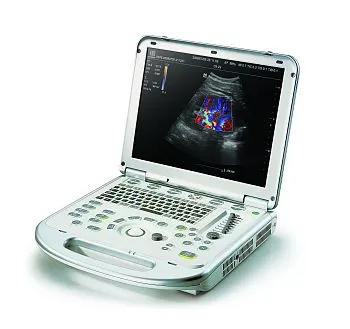

Клинические изображения

- Стандартные режимы сканирования: В-режим, М-режим, цветовое допплеровское картирование, энергетический допплер (включая направленный), импульсно-волновой допплер

- Стандартные режимы сканирования: В-режим, М-режим, цветовое допплеровское картирование, энергетический допплер (включая направленный), импульсно-волновой допплер

УЗИ аппарат LOGIQ e — это высочайшее качество визуализации, настоящая универсальность и компактность. Обновленная версия системы — LOGIQ e R9 — обеспечивает ещё более высокий уровень качества изображений для более широкого спектра комплексных исследований, включая интраоперационные и малоинвазивные вмешательства. Аппарат составит достойную конкуренцию стационарным системам среднего и высокого класса, как в плане возможностей, так и цены.

Систему отличает наличие датчиков со сверхвысокими частотами сканирования, эталонная чувствительность доплеровских режимов для сосудистых исследований, в том числе наиболее сложных транскраниальных, а также высокая частота кадров, которая необходима для качественных кардиологических исследований.

Портативный ультразвуковой сканер Logiq e одинаково эффективно решает диагностические задачи при проведении абдоминальных, сосудистых, кардиологических, акушерско-гинекологических исследований и исследовании поверхностных органов. Позволяет легко работать с разными пациентами от новорожденных до взрослых с «лишним весом».